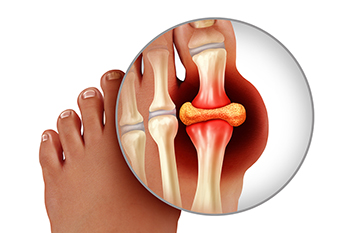

Preventing Gout Flare-Ups

Gout is a form of arthritis caused by the buildup of uric acid crystals in the joints, leading to sudden, intense pain, redness, and swelling, often in the big toe. The primary cause of gout is high levels of uric acid in the blood, which can result from certain foods, alcohol, or dehydration. To avoid flare-ups, it is important to limit foods that increase uric acid levels, such as red meat, shellfish, organ meats, sugary drinks, and alcohol, especially beer. Instead, focus on eating more fruits, vegetables, and whole grains, and drink plenty of water to help flush uric acid from the body. A podiatrist can help manage gout by diagnosing flare-ups, providing anti-inflammatory treatments, and recommending lifestyle changes, including dietary adjustments. In some cases, this type of doctor may prescribe medications to lower uric acid levels or prevent future attacks. If you have gout, it is suggested that you are under the care of a podiatrist who can help you to manage this painful condition.

Gout is a painful condition that can be treated. If you are seeking treatment, contact Peter Siroka, DPM from Connecticut. Our doctor will treat your foot and ankle needs.

What Is Gout?

Gout is a form of arthritis that is characterized by sudden, severe attacks of pain, redness, and tenderness in the joints. The condition usually affects the joint at the base of the big toe. A gout attack can occur at any random time, such as the middle of the night while you are asleep.

Symptoms

- Intense Joint Pain - Usually around the large joint of your big toe, and it most severe within the first four to twelve hours

- Lingering Discomfort - Joint discomfort may last from a few days to a few weeks

- Inflammation and Redness -Affected joints may become swollen, tender, warm and red

- Limited Range of Motion - May experience a decrease in joint mobility

Risk Factors

- Genetics - If family members have gout, you’re more likely to have it

- Medications - Diuretic medications can raise uric acid levels

- Gender/Age - Gout is more common in men until the age of 60. It is believed that estrogen protects women until that point

- Diet - Eating red meat and shellfish increases your risk

- Alcohol - Having more than two alcoholic drinks per day increases your risk

- Obesity - Obese people are at a higher risk for gout

Gout

Gout is a form of arthritis that is caused by a buildup of uric acid crystals in the joints. This considered to be one of the most frequently recorded medical illnesses throughout history. Gout occurrences in the US have risen within the past twenty years and the condition now affects 8.3 million people which is 4% of all Americans. Researchers have found that gout affects men more than women and African-American men more than white men.

Symptoms of gout are warmth, swelling, discoloration, and tenderness in the affected joint area. The small joint on the big toe is the most common place for a gout attack to occur.

People who are obese, gain weight excessively, drink alcohol heavily, have high blood pressure, or have abnormal kidney function are more likely to develop gout. Furthermore, certain drugs and diseases are likely to increase levels of uric acid in the joints which eventually leads to gout. You are also more likely to develop gout if you eat a lot of meat and fish.

Many who experience gout attacks will experience repeated attacks over the years. Some people who have gout symptoms, may never have them again, but others may experience them several times a year. If you have gout symptoms throughout the year, you may have recurrent gout. Those who have gout should also be careful about their urate crystals collecting in their urinary tract, because this may lead to kidney stones.

Diagnosis for gout is done by checking the level of uric acid in the joints and blood. Your podiatrist may also prescribe medicine to reduce uric acid buildup in the blood, which will help prevent any gout attacks.

To treat gout, your podiatrist may also prescribe you Anti-inflammatory medication (NSAIDs) which will relieve the pain and swelling of a gout episode and it can also shorten a gout attack. Maintaining a healthy diet is also a proven method to prevent gout attacks.